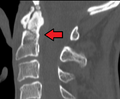

Type 3 odontoid fracture